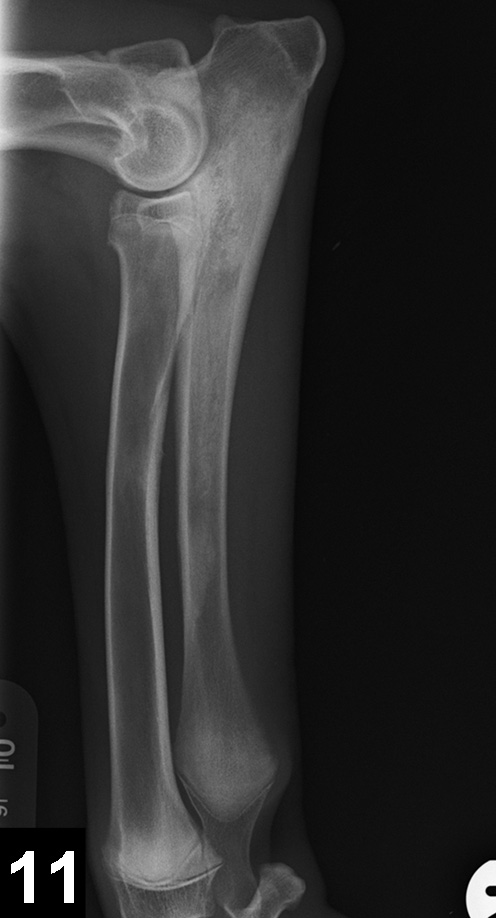

Figure 11. Mediolateral radiograph of the antebrachium in a 6-month-old German shepherd dog with shifting lameness. Patchy increased opacity within the medullary cavity of the ulnar diaphysis and proximal metaphysis suggest panosteitis.

5. Panosteitis

Panosteitis is a self-limiting inflammation of bone marrow in long bones. Large-breed dogs (particularly the German shepherd dog) are most commonly affected, although smaller breeds can also be affected. Males seem to be affected more frequently; most patients are between 5 and 12 months of age (range, 2 months–5 years).3 Affected dogs usually present with shifting lameness, which may range from mild lameness to inability to walk. Clinical signs include pain on palpation of the affected long bones, especially in the forelimb. Radiographic findings vary, depending on disease stage, but increased medullary densities at the level of the nutrient foramen and periosteal reaction are common (Figure 11). Clinical signs typically resolve by 18 to 20 months of age. Treatment does not appear to influence the outcome and consists of supportive measures (eg, rest, analgesics).